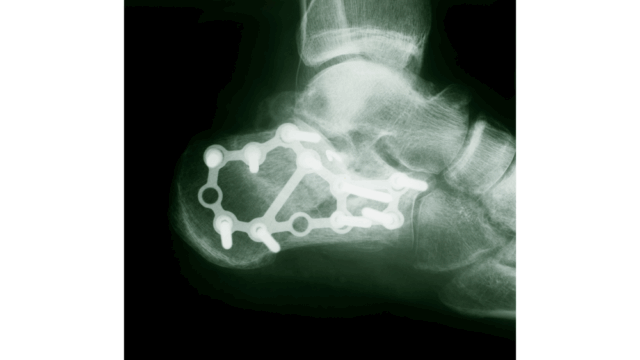

กระดูกส้นเท้าแตก